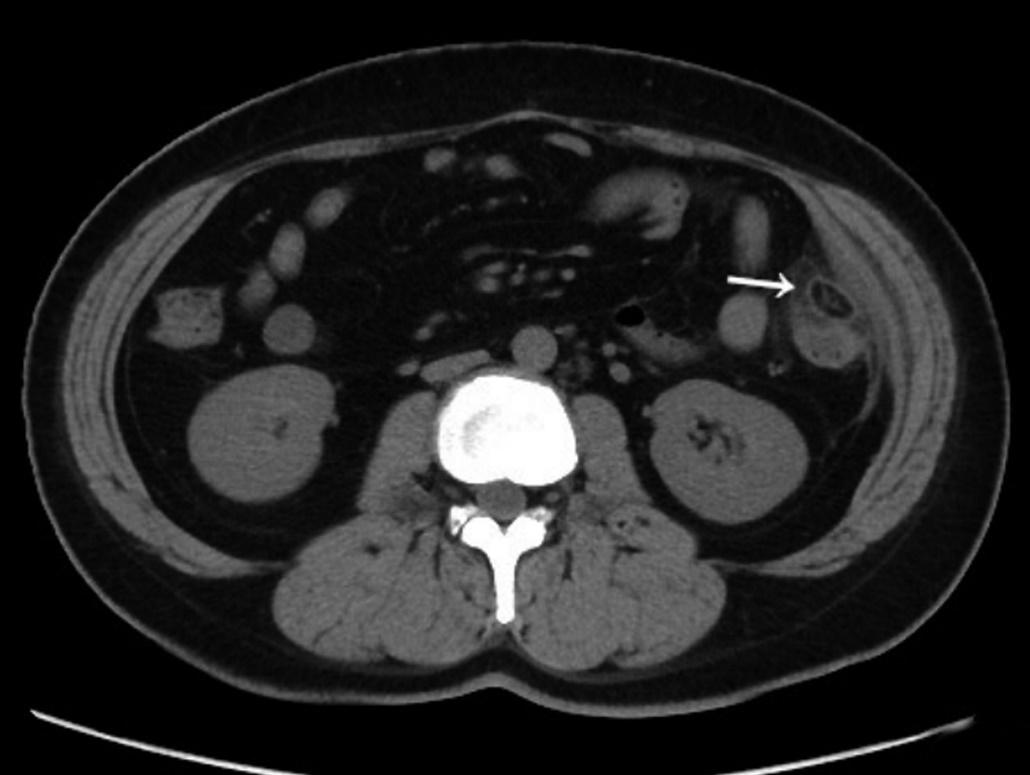

(1)急性肠系膜脂膜炎:急性肠系膜脂膜炎病灶范围较大,CT平扫可见局限性脂肪密度增高影或肿块影(位于系膜区,大部分小肠系膜,也可以是结肠系膜),病灶包绕但不侵犯肠系膜血管,可形成“假肿瘤包膜征”、“脂肪晕环征”;而急性肠脂垂炎呈与肠管相连、范围较小的局灶性病灶,一般不累及小肠系膜。

上图是非常典型的肠系膜脂膜炎CT图像。CT平扫病灶位于小肠系膜,推挤周围肠管,密度明显高于腹膜后正常脂肪密度,呈脂肪性包块,包绕肠系膜血管,弯箭所示包块边缘,直箭所示“小结节”及其周围“脂环征”。